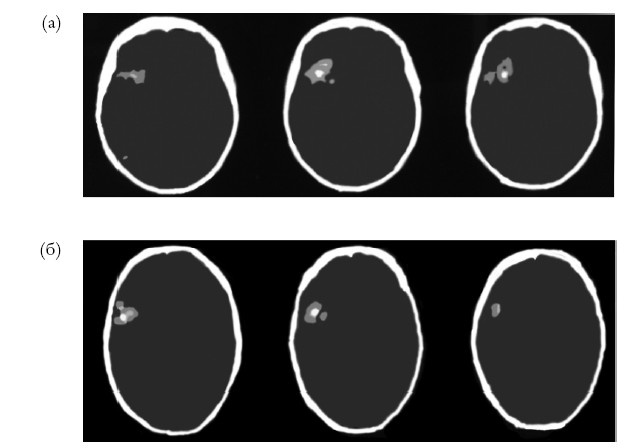

Результаты этого сравнения подтвердили, что правое полушарие особенно активно на ранних стадиях открытия как общего принципа, так и специфических правил Висконсинского теста, в полном соответствии с гипотезой новизны-привычности. Точнее, правые префронтальные области были активными на ранних стадиях «открытий» обоих типов, что опять возвращает нас к лобным долям (рис. 6.2).

Иллюстрация к книге — Креативный мозг. Как рождаются идеи, меняющие мир [i_013.jpg]

Рис. 6.2. Визуализация при помощи функциональной магнитнорезонансной томографии (фМРТ) во время выполнения Висконсинского теста сортировки карточек (WCST). (а) Области, более активные во время выполнения первых трех, чем последних трех категорий. (б) Области, более активные во время выполнения первой половины, чем второй половины каждой категории

Эти данные согласуются с другими, опубликованными в некоторых исследованиях с использованием фМРТ. По результатам работы Корбетты и Шульмана, правая вентролатеральная часть префронтальной коры является критической для переключения и перенаправления внимания к новой цели. В то же время левая вентролатеральная часть префронтальной коры играет важную роль в извлечении сводной, ранее полученной информации из долгосрочной памяти, в соответствии с идеей, о которой мы говорили в Главе 3, связывая левое полушарие с сохранением информации, поступившей ранее7. Согласно этим данным, «сеть внимания», которая, как предполагают, направлена во внешний мир, имеет более сильные связи и более специализирована в правом полушарии8.